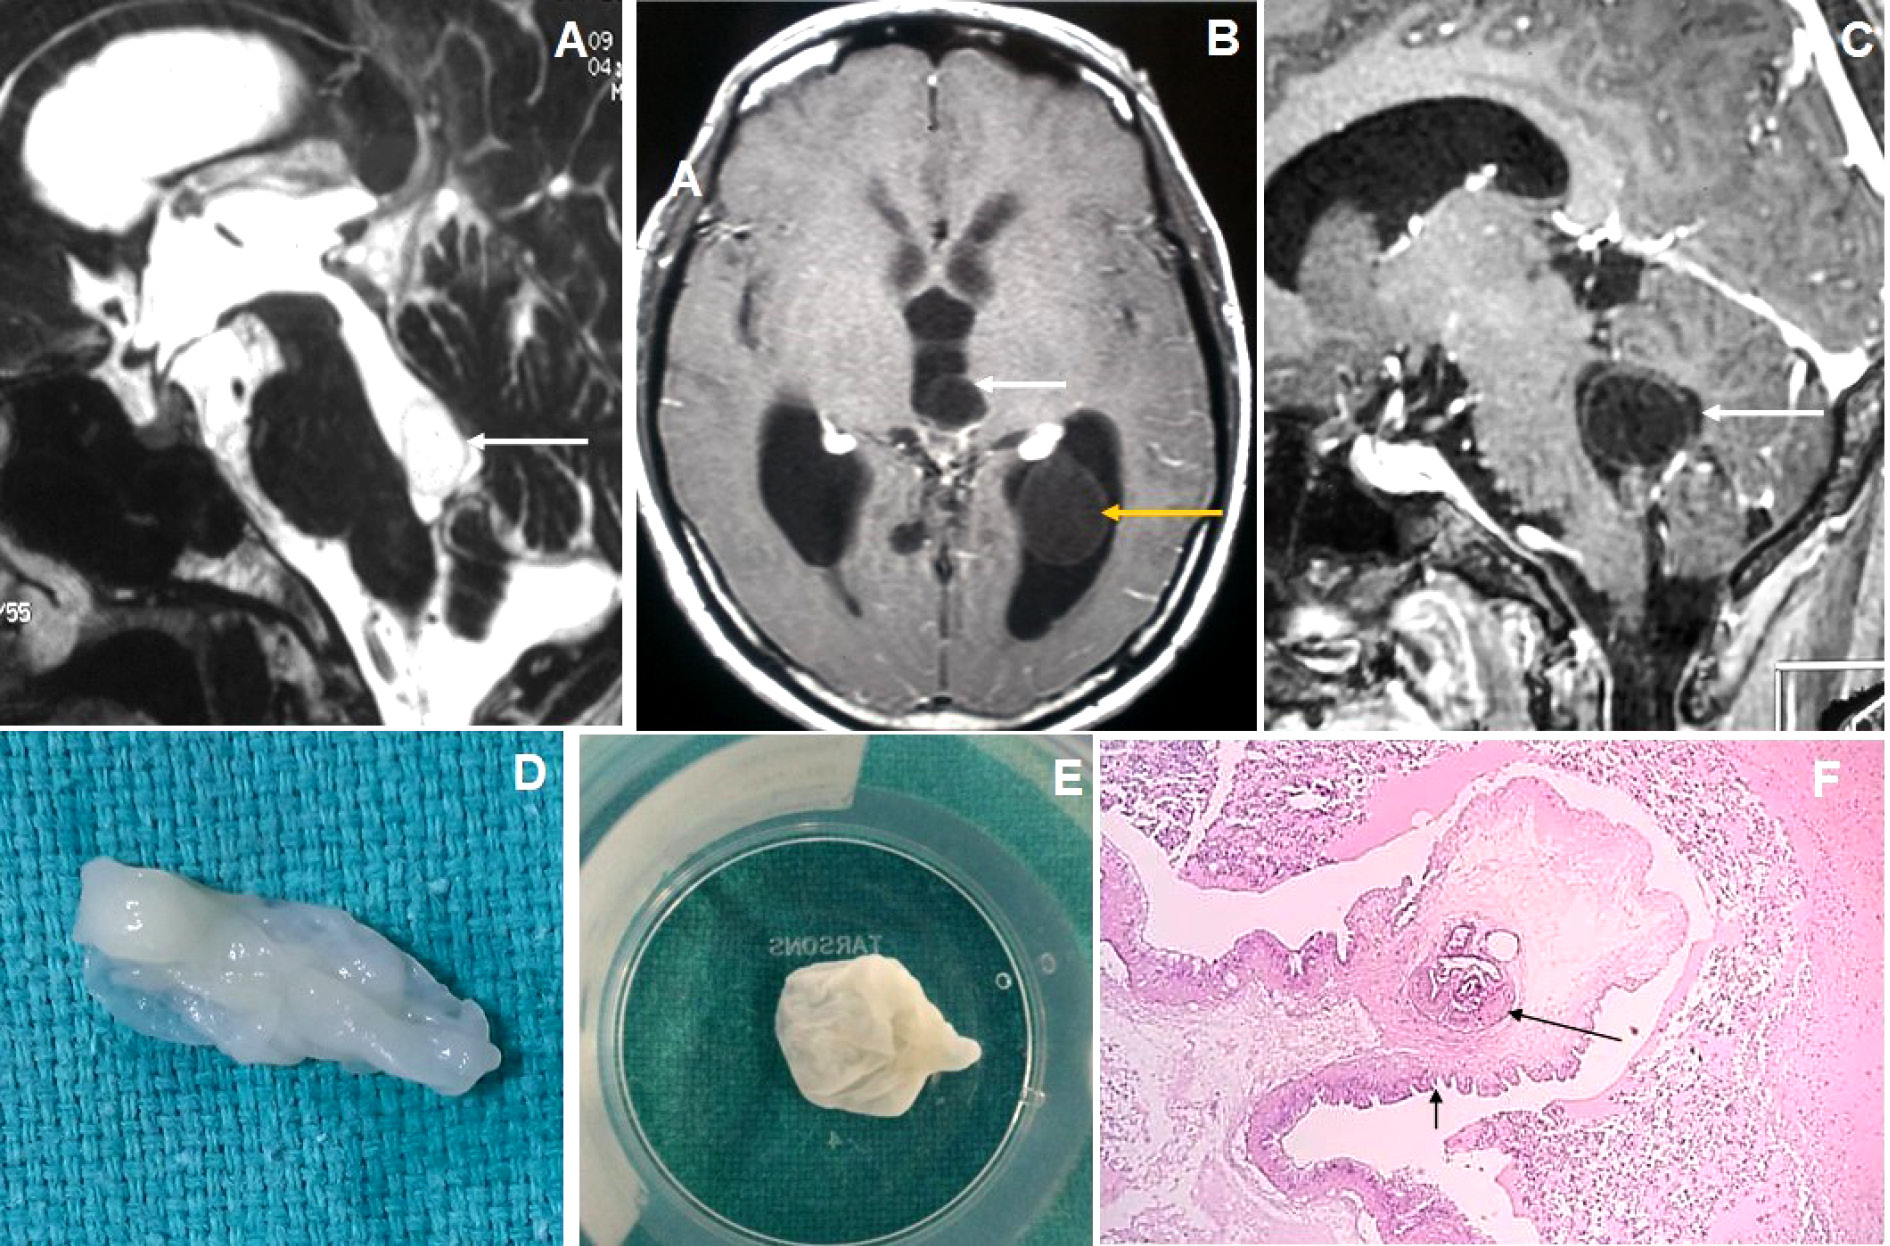

Figure 5. Brain magnetic resonance imaging of 80 years male with headache and visual disturbance. (A) Sagittal T2WI image shows a thin-walled T2 hyperintense cysticercus lesion in the fourth ventricle (arrow) causing supratentorial hydrocephalus. (B-C) Axial and sagittal T1W post-contrast images show cysticercus lesions within the 3rd ventricle (white arrow in image B), trigone of the left lateral ventricle (yellow arrow) and fourth ventricle (arrow in image C). (D-E) Neuroendoscopic post-excision cysticercus specimen shows thin-walled cystic lesions. (F) HPE image shows sucker (long arrow) and cuticle (short arrow) of the cysticercus lesion.